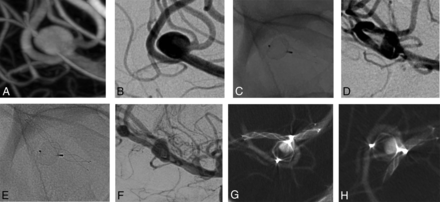

All aneurysms and patients underwent at least 1 VasoCT during the follow-up, showing partial WEB opacification without neck or aneurysm opacification (Fig 2) in 3 patients (patients 2, 5, and 6), complete WEB opacification without neck or aneurysm opacification (Fig 3) in 3 patients (patients 1, 7, and 8), partial WEB opacification and neck opacification (Fig 4) in 1 patient (patient 3), and complete WEB opacification and dome opacification (Fig 5) in 1 patient (patient 4). This last patient was treated with an inappropriately oversized (mean aneurysm width, 6.7 mm, and the implanted device was a WEB 17 SL 7 × 3 mm) WEB device.

3D (A) and 2D (B) DSA show an MCA aneurysm. Nonsubtraction (C) and subtraction (D) images of the first DSA follow-up after 6 months and of the latest DSA follow-up after 2 years (E and F) show partial opacification of the WEB and the aneurysm sac, confirmed by VasoCT in 2 different views (G and H).

3D (A) and 2D (B) DSA show an MCA aneurysm. Nonsubtraction (C) and subtraction (D) images of the first DSA follow-up after 6 months and of the latest DSA follow-up after 1 year (E and F) show complete opacification of the WEB and the aneurysm dome, confirmed by VasoCT in 2 different views (G and H).